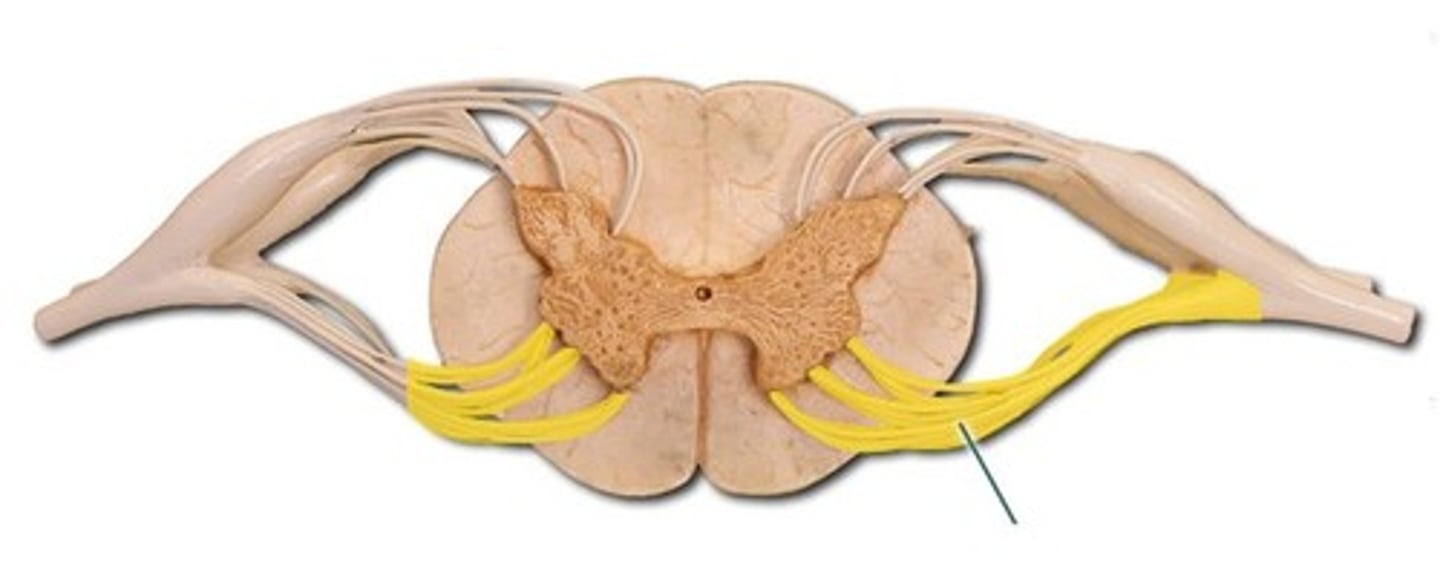

anterior (ventral) root (of spinal cord)

central canal (of spinal cord)

conus medullaris

gray matter (of spinal cord)

cauda equina

dorsal root ganglion (spinal)

posterior (dorsal) root (of spinal cord)

spinal nerve

white matter (of spinal cord)